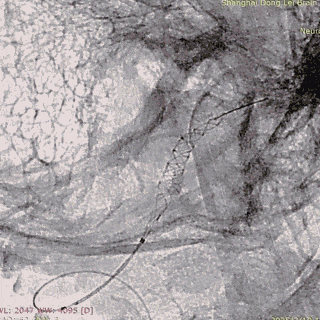

强易达(Choydar)血流导向密网支架头端封闭结构,减少对血管壁的损伤,安全性好。

独特热处理技术增强了贴壁性。整体释放操作简单,无需过多推挤,显影清晰。

强易达(Choydar)血流导向密网支架2-3mm直径可通过其0.017微导管输送系统释放,通过性好,在此病例中也减少了更换微导管带来的操作和风险。

强易达(Choydar)血流导向密网支架打开贴壁良好,2mm和3mm支架在不同血管直径中均展现了良好的贴壁,小血管中表现优异。2mm-6.5mm直径可选,型号多,应用范围广。